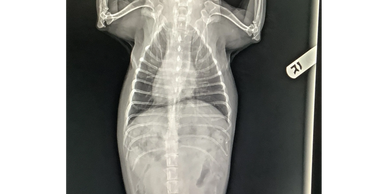

We are able to do basic x-rays including OFA